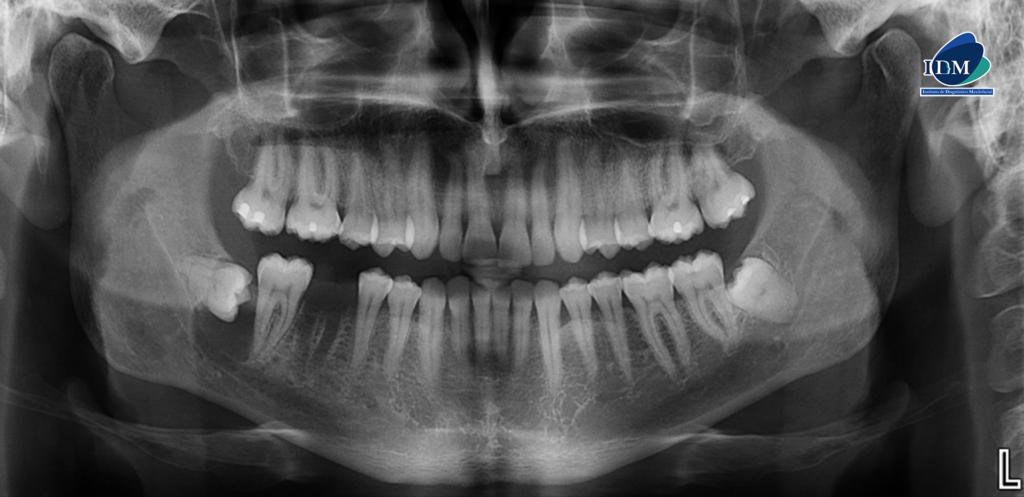

En la radiografía panorámica (Figura 1), se aprecia imagen radiolúcida unilocular para coronaria mesial, de limites definidos, bordes parcialmente corticalizados, que se extiende en sentido cefálico caudal desde cima del reborde alveolar hasta cortical inferior del conducto dentario inferior, en sentido mesio distal desde distal de pieza 47 hasta tercio cervical radicular de pieza 48, que ocasiona el borramiento de la lámina dura de pieza 47 y compromete el conducto dentario inferior.

Radiografia Panorámica